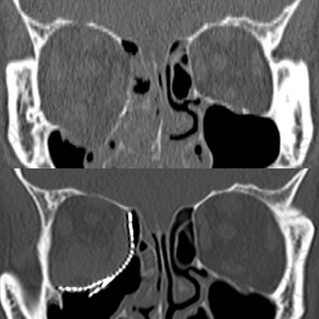

FRACTURAS ORBITARIAS